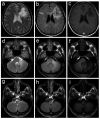

Progressive multifocal leukoencephalopathy is caused by the JC polyomavirus (JCV) and is one of the most feared complications of HIV-1 infection. Unlike other opportunistic infections, this disease can present when CD4 counts are higher than those associated with AIDS and when patients are receiving combined antiretroviral therapy, either shortly after starting or, more rarely, during long term successful treatment. Clinical suspicion of the disease is typically when MRI shows focal neurological deficits and associated demyelinating lesions; however, the identification of JCV in cerebrospinal fluid or brain tissue is needed for a definitive diagnosis. Although no specific treatment exists, the reversal of immunosuppression by combined antiretroviral therapy leads to clinical and MRI stabilisation in 50-60% of patients with the disease, and JCV clearance from cerebrospinal fluid. A substantial proportion of patients treated with combined antiretroviral therapy develop inflammatory lesions, which can be associated with either a favourable outcome or clinical worsening. The reasons for variability in the natural history of progressive multifocal leukoencephalopathy and treatment responses are largely undefined, and more specific and rational approaches to management are needed.